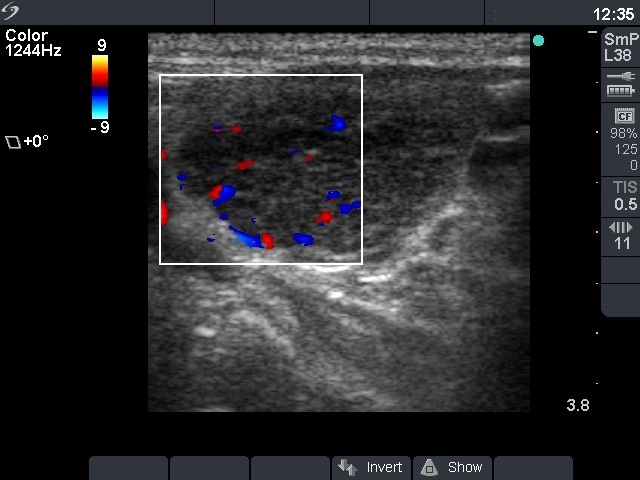

Chronic lymphocytic thyroiditis - Case 50. (ultrasonographic picture 3)

Left lobe, longitudinal scan, color Doppler mode. Type 3 vascular pattern.